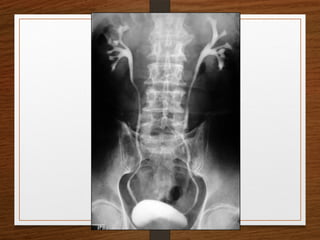

What are the D/D of a radiopaque shadow in this region?

• Kidney stone

• Gallstones

• Pancreatic calculi

• Foreign body

• Fecolith

• Phleboliths

• calcified lymph node

• calcified renal tuberculosis

• calcified adrenal gland

• chip fracture of a transverse process of vertebra or calcification of costal

cartilage